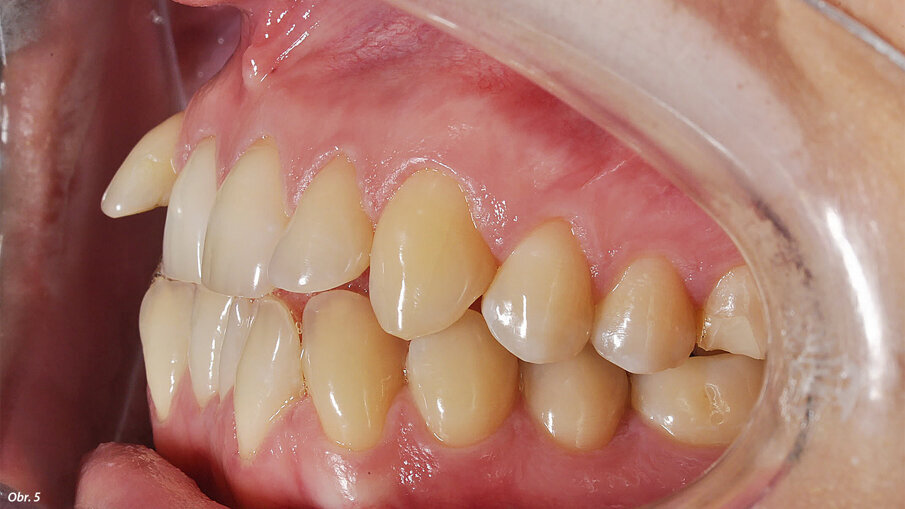

Vyšetřením jsme zjistili výrazný nedostatek místa v horní i dolní frontě. Zub 12, s meziodistální šířkou 6,25 mm, byl eruptován vestibulárně zcela mimo zubní řadu se současným posunem horní středové linie doprava. Mezera mezi zuby 11 a 13 činila 1,5 mm. Nedostatek místa v dolním zubním oblouku činil 2,6 mm resp. 2,85 mm ve dvou dolních kvadrantech. V transverzálním rozměru byl oproti normě menší jak anteriorně, tak i posteriorně. Oproti tomu skus laterálně a v místě špičáků byl normální – zde jsme diagnostikovali I. třídu podle Anglea. Hloubka skusu byla 0,5 mm s tendencí k otevřenému skusu. Incizální schůdek byl 0 mm se skusem hrana na hranu u zubů 11/41 a 21/31/41. Podle Boltnových indexů byl přítomen nepoměr v šířce zubů s přebytkem „zubního materiálu“ v dolní čelisti (obr. 3–5). Při skeletální diagnostice jsme nalezli disharmonii ve velikosti čelistí s retrognátní horní čelistí a ortognátní mandibulou – III. skeletální třída s úhlem ANB -2,3° a hodnotou WITS o velikosti -3,9 mm. U vertikální analýzy byl zřejmý mírně horizontální typ růstu s hodnotou SpP/MeGo 23° a poměrem SGo/NMe 71 % na základě anteriorní inklinace horní čelisti. Interincizální úhel byl lehce zvětšený, což bylo dáno mírnou protruzí horních řezáků spolu s retrudovaným postavením dolních řezáků (obr. 6, 7).

EIntraorální fotografie počátečního stavu pacientky.